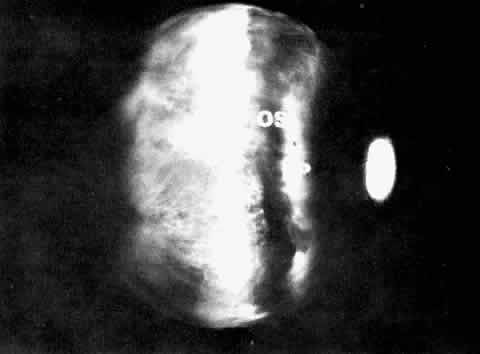

Fig. 14. Ora serrata in young adult, showing abrupt junction of ciliary nonpigmented

epithelium and sensory retina. A few hyalocytes are present in the

adjacent vitreous, and a degenerative cyst (C) is present in the peripheral

retina. (Toluidine blue, X 200) Fig. 14. Ora serrata in young adult, showing abrupt junction of ciliary nonpigmented

epithelium and sensory retina. A few hyalocytes are present in the

adjacent vitreous, and a degenerative cyst (C) is present in the peripheral

retina. (Toluidine blue, X 200)